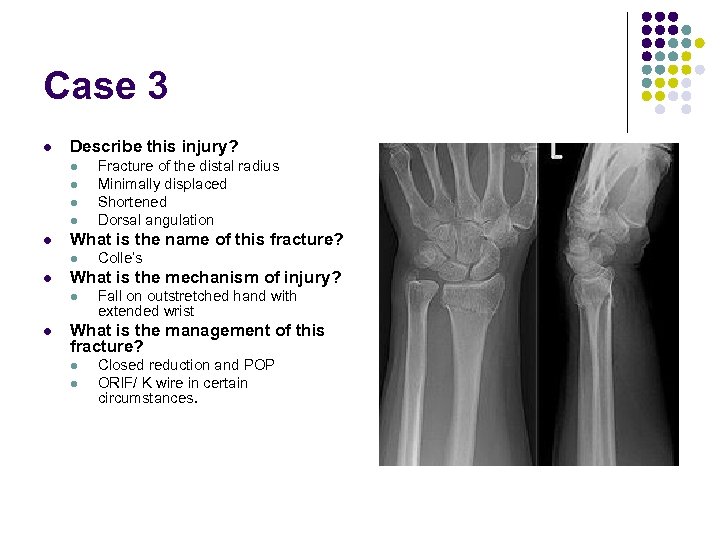

Case 3 l Describe this injury? l l l What is the name of this fracture? l l Colle’s What is the mechanism of injury? l l Fracture of the distal radius Minimally displaced Shortened Dorsal angulation Fall on outstretched hand with extended wrist What is the management of this fracture? l l Closed reduction and POP ORIF/ K wire in certain circumstances.